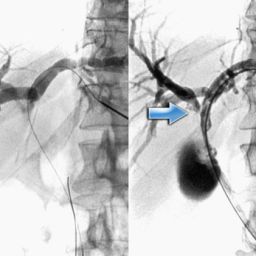

- Ultrasound: A non-invasive imaging technique that can detect abnormalities in the liver and bile ducts.

- Magnetic Resonance Cholangiopancreatography (MRCP): A specialized MRI technique that provides detailed images of the bile ducts.